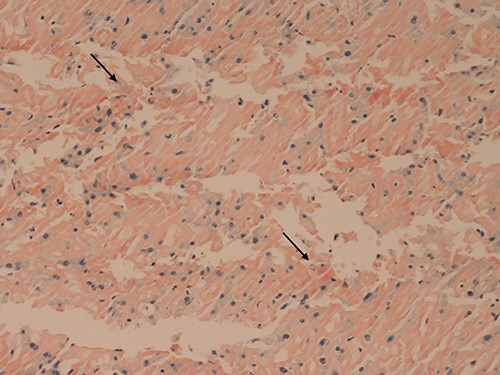

Her liver biochemistry continued to deteriorate so a transjugular liver biopsy was performed. Histology from both liver and duodenal biopsies was consistent with amyloidosis on Congo red staining (Figs 1 and 2, respectively). A subsequent bone marrow biopsy, organized by the haematologists, revealed a low level infiltrate of plasma cells consistent with multiple myeloma.

Small bowel mucosa (Congo red, x20): the substance is positive with Congo red stain in keeping with amyloid (salmon pink staining under standard light microscopy).